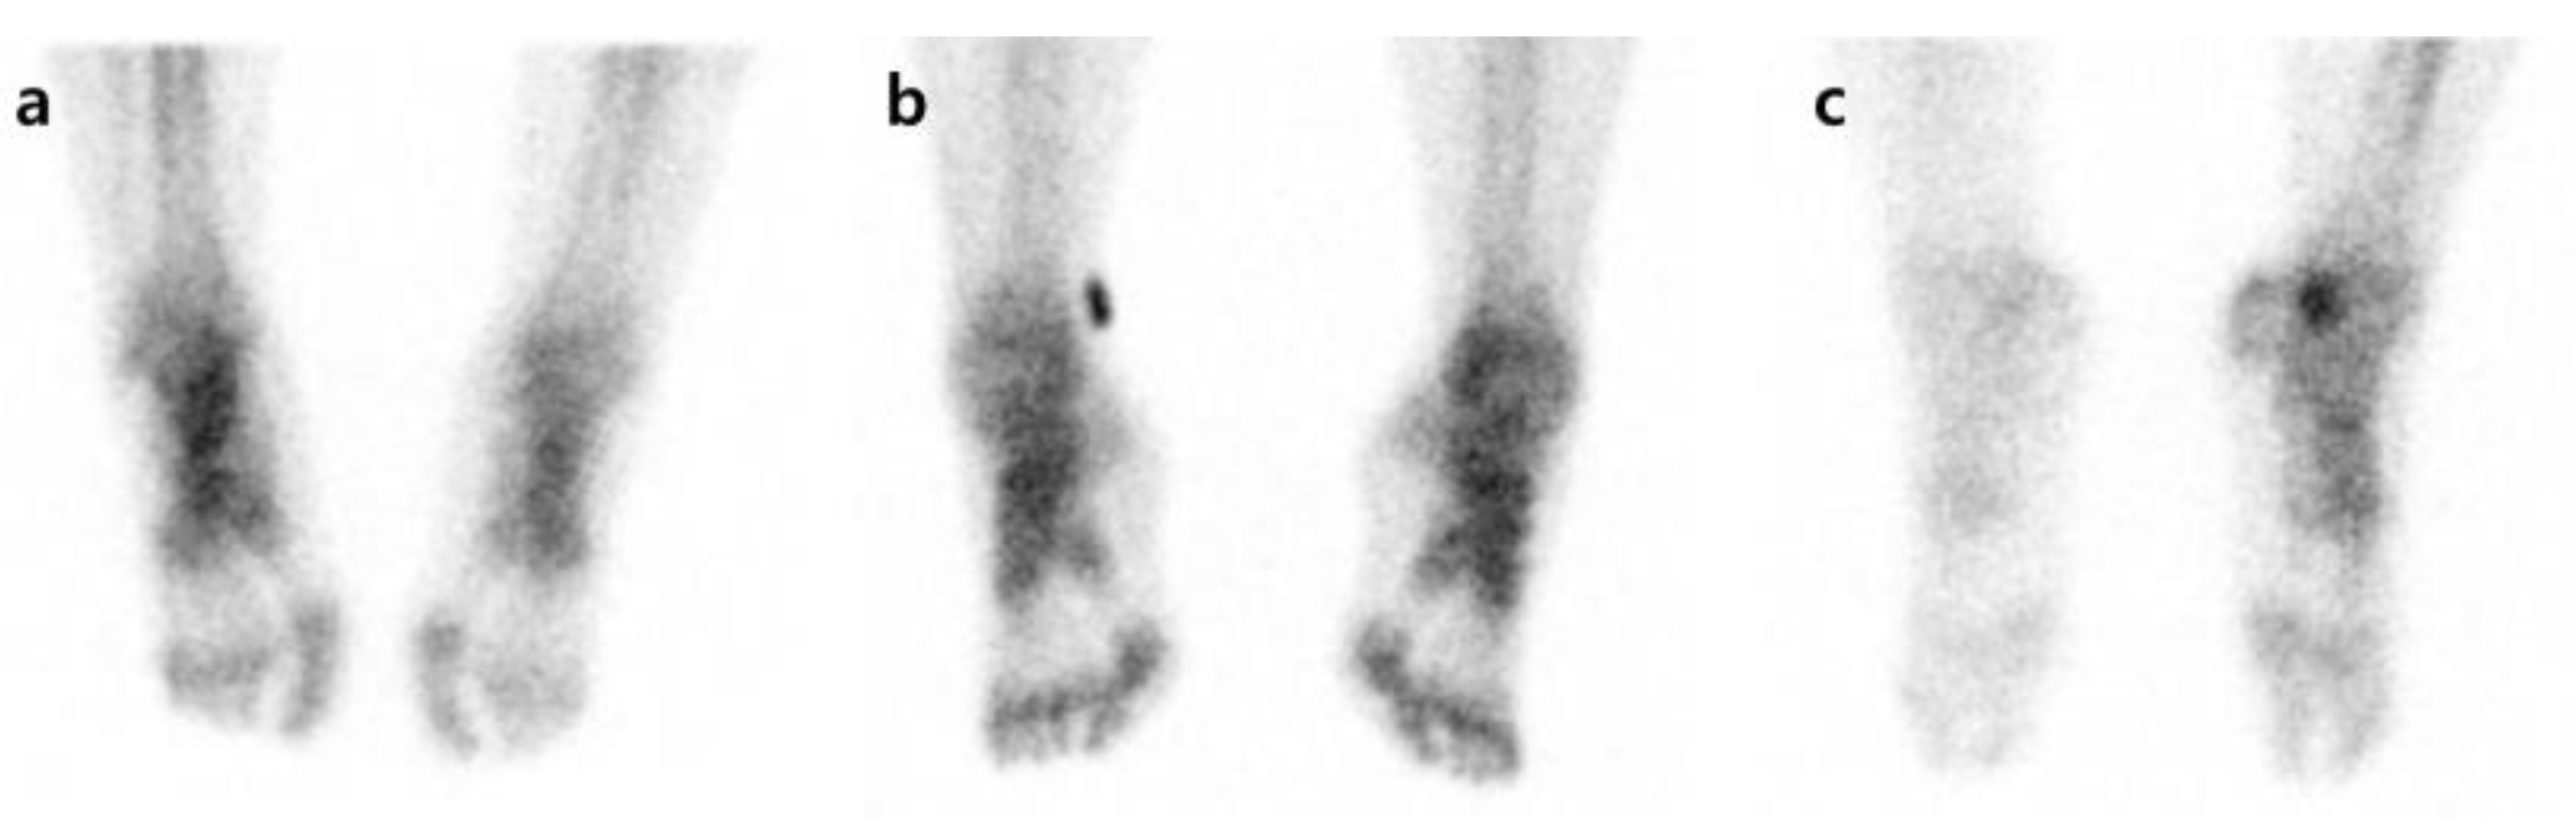

Pattern analysis was carried out by comparing degrees of radiotracer uptake in the affected side with the unaffected side for each phase. First, in each phase, an increase in radioactivity in affected extremities compared with contralateral extremities was defined as I. When the unaffected side and the affected side showed symmetric uptake, it was defined as S, and when the uptake in the affected side decreased compared to the unaffected side, it was defined as D (Figure 1). Overall, 27 patterns (I-I-I, I-I-S, I-I-D, I-S-I, I-S-S, I-S-D, I-D-I, I-D-S, I-D-D, S-I-I, S-I-D, S-I-S, S-D-I, S-D-S, S-D-D, S-S-S, S-S-D, S-S-I, D-I-I, D-I-S, D-I-D, D-S-I, D-S-S, D-S-D, D-D-I, D-D-S, and D-D-D) were created by combining the uptake patterns of each phase. An increase or decrease in the radiotracer uptake of the affected side compared to the unaffected side in phases 1, 2, or 3 was defined as an abnormal finding. As there is no typical pattern to diagnose CRPS by TPBS, we followed the method by Moon et al. [21]. After the pattern analysis, the cases showing I-I-I, S-S-I, D-D-I, D-D-S, and D-D-D patterns were determined as the CRPS group. If the radioactive uptake pattern was locally increased rather than in a diffuse way, it was regarded as a change due to a disease unrelated to CRPS, such as arthritis, and was considered as non-CRPS [22].

Figure 1. Examples of uptake pattern in three-phase bone scintigraphy. All patients have symptoms in the right foot. (a) Increased uptake on affected side, (b) no difference between affected and unaffected sides, (c) decreased uptake on affected side.